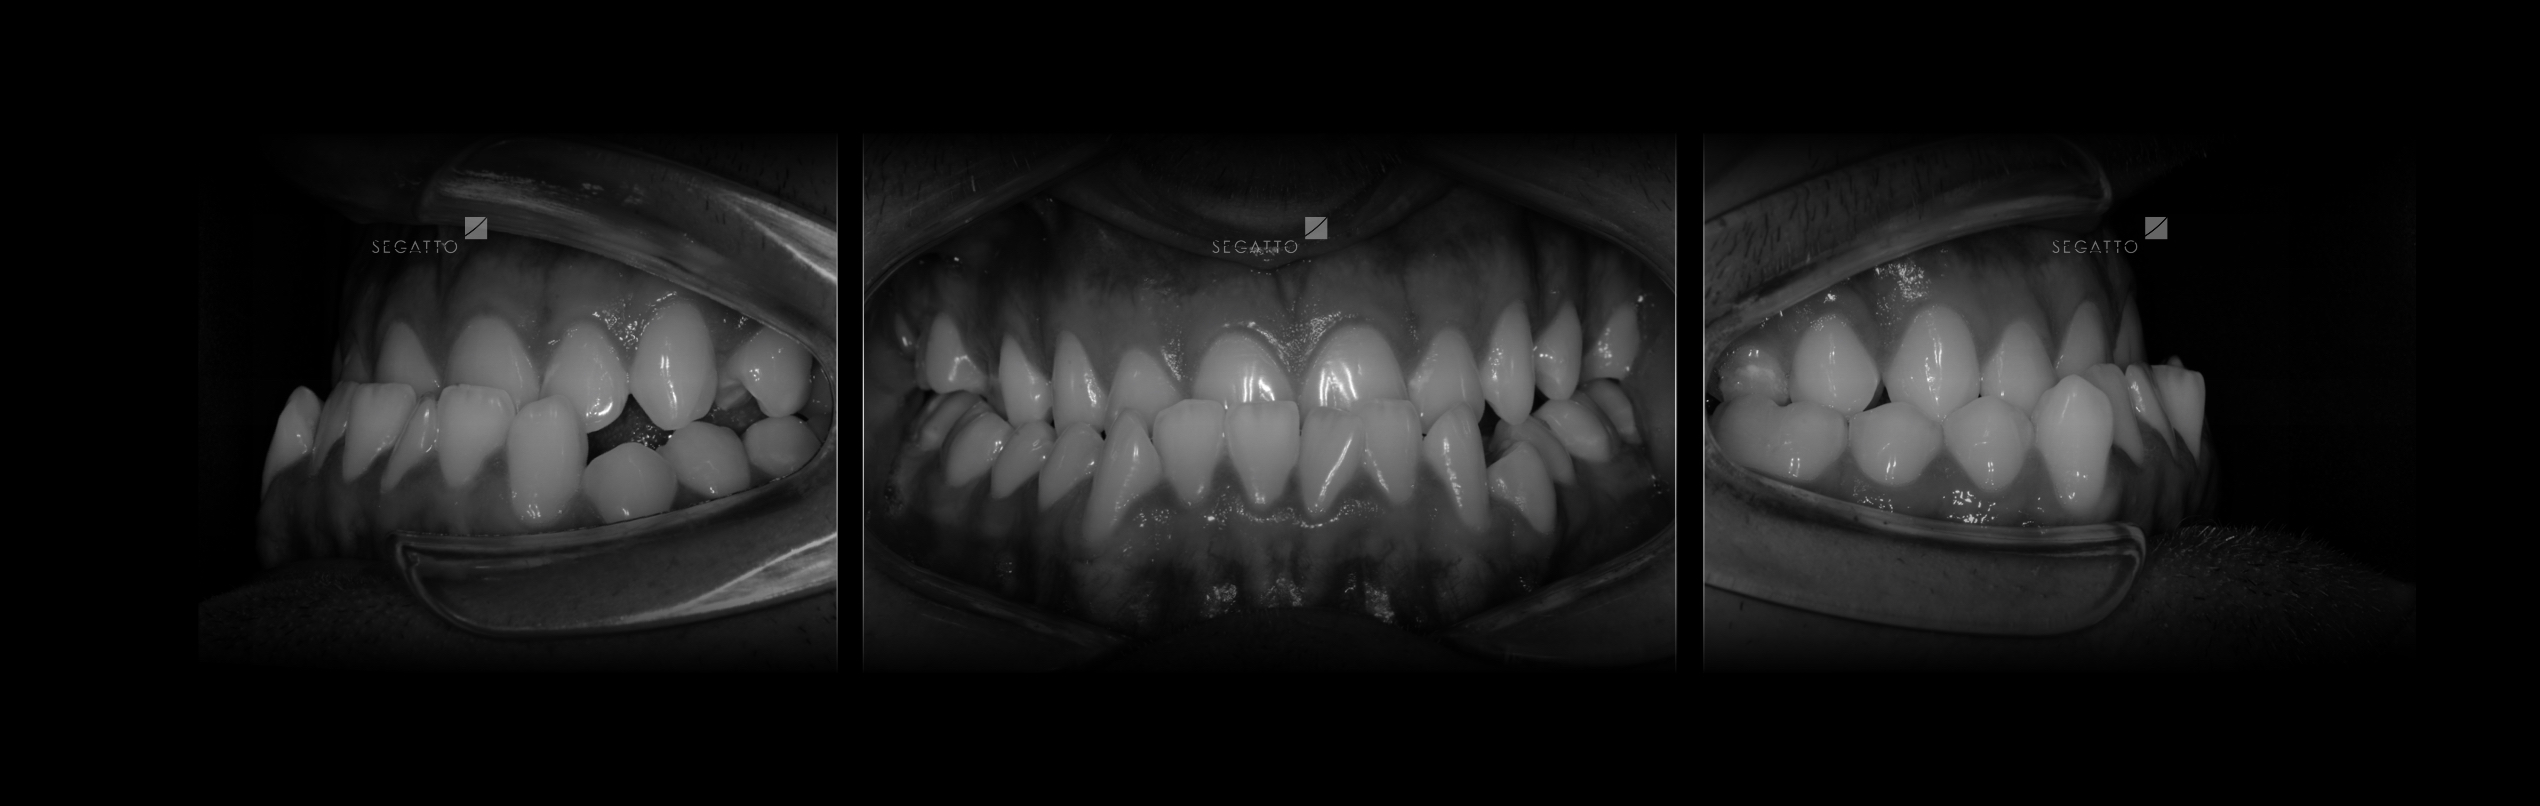

Orthodontics

Cases